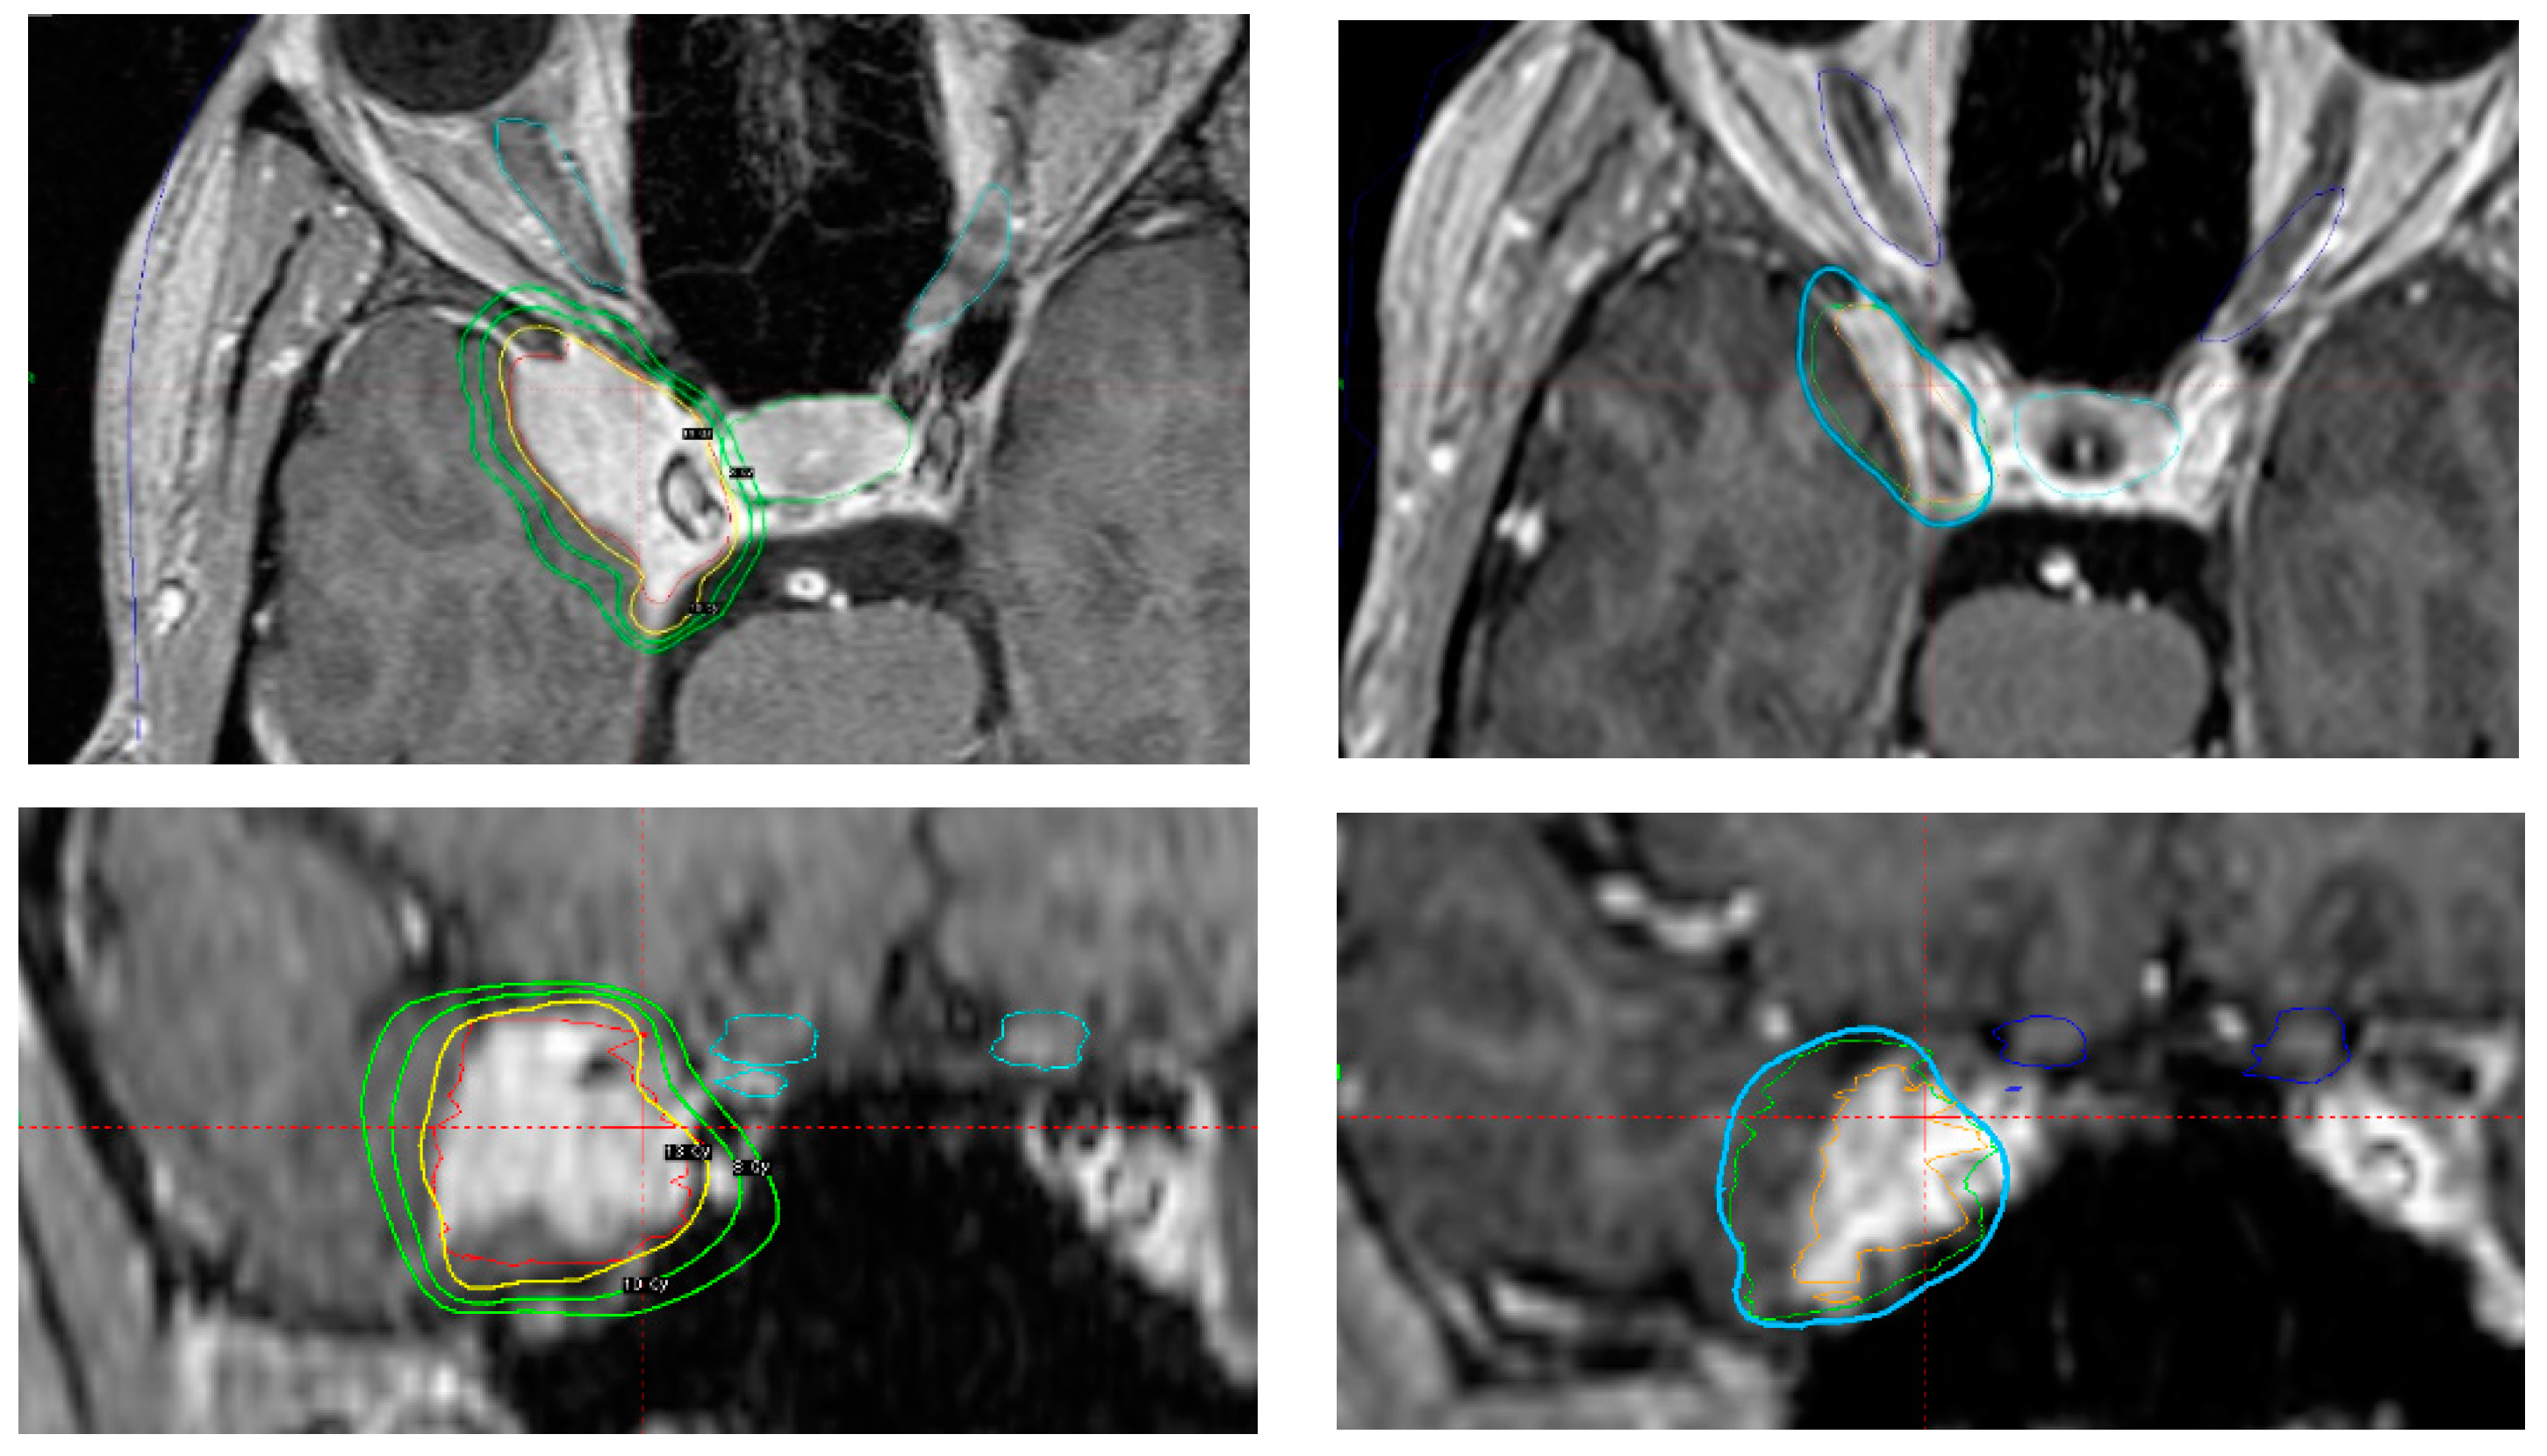

4.4. Challenging Aspects Related to SRS